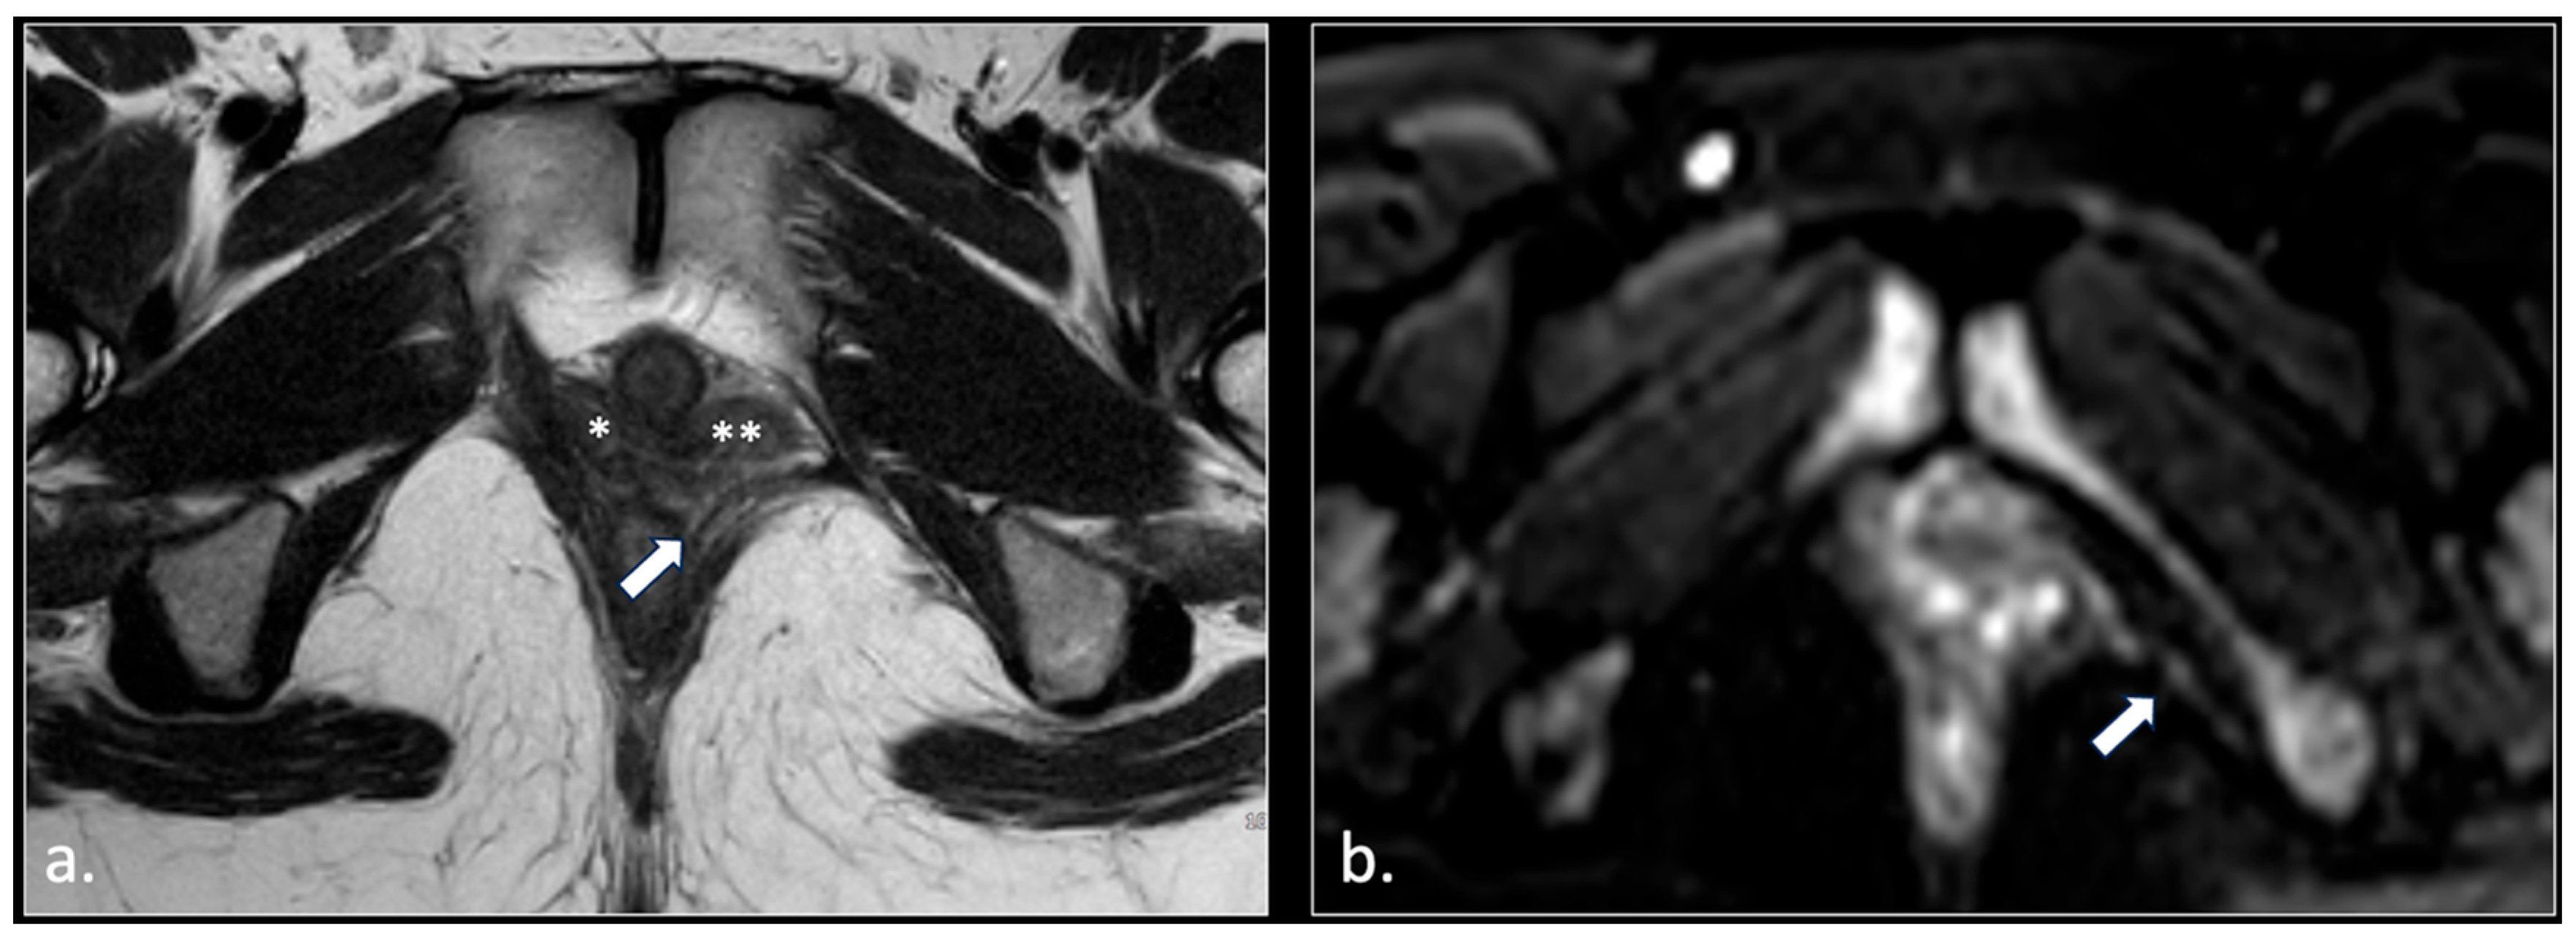

- Pudendal nerve schwannomas (2 patients);

- Varices of the pudendal vein in the Alcock canals (2 patients).